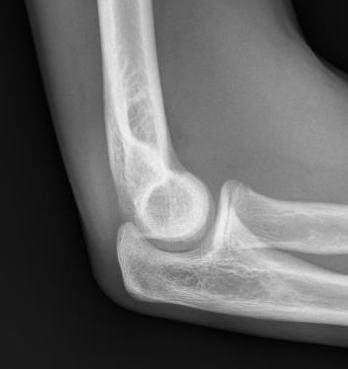

Xray

Displaced medial epicondyle fracture